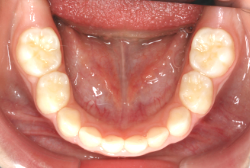

叢生(そうせい)

凸凹な歯並びのことを叢生といいます。矯正歯科に来院する患者様の主訴の中で、最も多いのが「配列の凸凹を真っ直ぐにしたい」というものです。歯の大きさと顎の大きさの調和がとれていないことが原因です。

凸凹を主体としたケースの場合、当院の平均治療期間は18ヶ月ですので、このケースは少し長めに経過しました。理由の一つは凸凹の程度がかなり重症だったと言うことですが、もう一つは、右下第2大臼歯が45度くらい前傾していたため、それを整直化させるために時間を要したと考えています。いずれにしても最終結果は大変よい状態と思います。

治療前は並びが乱れて見た目が悪いというのはもちろん問題ですが、歯科医学的に一番困るのは噛み合わせが悪いという点です。上下の犬歯(3番目の歯)は、上下的に離れた位置にあるため接触することができません。つまり歯としては存在していても、歯としては機能していないということです。